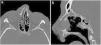

All NOE fractures are made up of a single fragment or a series of comminuted fragments split along the five cardinal tracts. These five cardinal tracts are the lateral surface of the nasal bone together with the piriform aperture, tracts which cross the medial maxillary buttress, the inferior orbital rim together with the floor of the orbit, the medial wall of the orbit and the frontomaxillary suture. An NOE fracture must involve at least four for these five cardinal lines, so they must be specifically sought out in cases where there is doubt regarding the existence of an NOE fracture pattern21–24 (Fig. 5).

(A) Representation of the five cardinal lines of the NOE region: nasal bone and piriform aperture (blue), medial maxillary buttress (yellow), floor of orbit (green), medial wall of orbit (purple) and frontomaxillary suture (red). (B and C) Axial computed tomography (CT) with a bone window and 3D reconstruction. Comminuted left NOE fracture with displaced and depressed fragments. Involvement of the nasolacrimal duct (arrow tip). Palpebral emphysema and blood in the sinus. (D and E) Axial CT with a bone window and 3D reconstruction. Left NOE fracture with large fragment without displacement. Fracture of the left maxillary sinus with blood in the sinus and the external wall of the left orbit (arrow tip).

Clinically, they are characterised by depression of the root of the nose (saddle nose) and there may be associated exophthalmos due to an increase in intraorbital volume, telecanthus (increased distance between the medial canthus of each eye) due to lesion of the medial canthal ligament, or rhinorrhoea and anosmia due to lesion of the cribiform plate.

Anatomically, the importance of the aforementioned medial canthal ligament, which laterally joins the tarsus of the upper and lower eyelids and medially inserts in the region of the lacrimal crests in the medial orbit, is worth noting.21,25

Although the medial canthal ligament cannot be seen in computed tomography (CT), the specific degree of comminution in its bone insertion together with the clinical examination are very important data with regard to surgical planning.

In addition to the tendon, attention should also be paid to the nasolacrimal duct and lacrimal sac, the olfactory nerve and the ethmoid vessels.